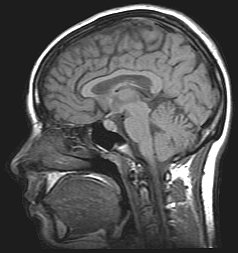

The leading experimental technique for studying proactive interference in the brain is the "recent-probes" task. Initially, this is when participants must commit a set of items to memory. They then ask them to recall a specific item. Assessing them is shown by a probe.[10] Thus, using recent-probes task and fMRIs, the brain mechanisms involved in resolving proactive interference identify as the ventrolateral prefrontal cortex and the left anterior prefrontal cortex.[11]

Retroactive Interference has been localized to the left anterior ventral prefrontal cortex by magnetoencephalography (MEG) studies investigating Retroactive Interference and working memory in elderly adults.[23] The study found that adults 55–67 years of age showed less magnetic activity in their prefrontal cortices than the control group. Executive control mechanisms are located in the frontal cortex and deficits in working memory show changes in the functioning of this brain area.[23]